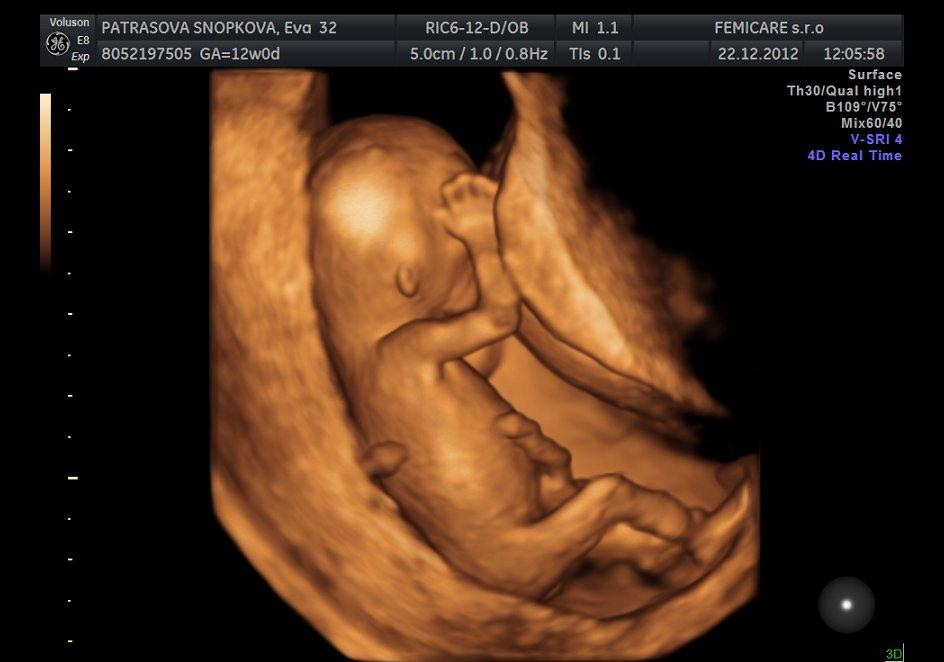

To je kraaaaaaaaaaaaaaaaaaaaaasa,uzasne babatko.Blahozelam. 🙂 Krasne je. 🙂

@michaelamia1902 ahoj,to ti robili uz 3D ultrazvuk?